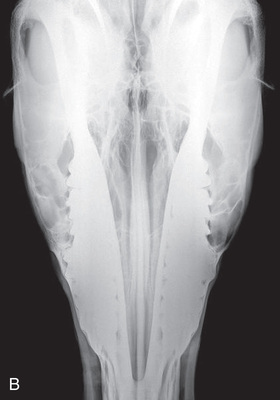

| Skull | Lateral (Fig. 24.52) | Against the affected side. | Opposite lateral side. | From the opposite side on area of interest. | |

| Skull | Dorsoventral (DV) (Fig. 24.53) | Horizontal ramus against the ventral aspect of the mandible. | At the dorsal aspect. | Along the midline of dorsal skull on area of interest, perpendicular to the horizontal ramus of mandible. | Easier to note asymmetry. Will need increased exposure. |